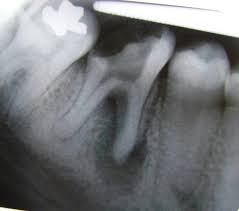

Fractura Radicular Vertical

Una fractura radicular vertical es una fisura que se extiende a lo largo de la raíz del diente, a menudo causada por un trauma o una presión excesiva.

Los pacientes suelen sentir dolor al morder y pueden notar hinchazón.

La fractura generalmente requiere la extracción del diente, ya que es difícil de reparar. Es crucial tratarla rápidamente para evitar infecciones.